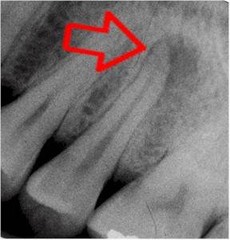

internal resorption

-round to ovoid radiolucency in the central part of the tooth -chronic inflammation -may see pinkish hue to crown if it is involved